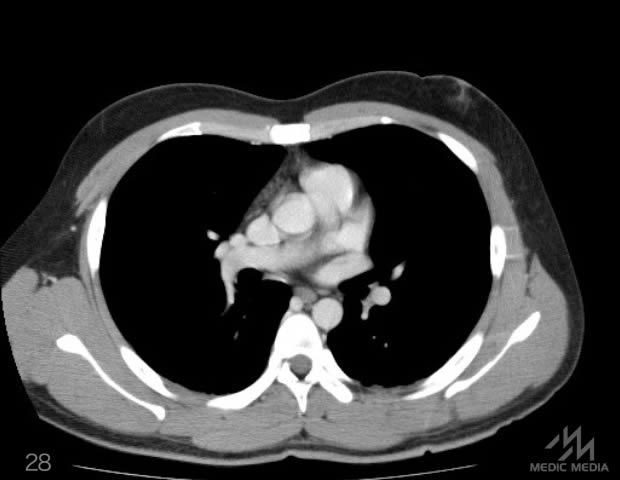

造影CT

スライド(画像下)を動かしながら,CTで臓器の位置を確認してみましょう.

消化器